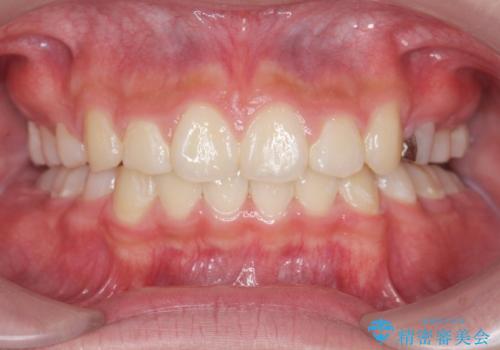

[ マウスピース矯正治療 ] がたつき ねじれのある前歯をきれいにしたい

![[ マウスピース矯正治療 ] がたつき ねじれのある前歯をきれいにしたいの症例 治療前](https://seimitsushinbi.jp/wp/wp-content/uploads/2025/04/8438e7299f1b9566ac213e8e9f7db5f6-500x350.jpg?v=1745226068)